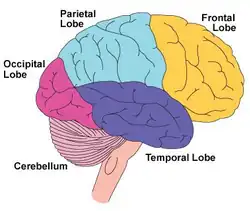

| Illustration of lateral view of the right side of the brain showing the frontal lobe, other lobes of the brain, and the cerebellum | |

The frontal lobe contains the precentral gyrus and prefrontal cortex and, by some conventions, the orbitofrontal cortex. These three areas are represented in both the left and the right cerebral hemispheres. The precentral gyrus or primary motor cortex is concerned with the planning, initiation and control of fine motor movements dorsolateral to each hemisphere.[15] The dorsolateral part of the frontal lobe is concerned with planning, strategy formation, and other executive functions. The prefrontal cortex in the left hemisphere is involved with verbal memory while the prefrontal cortex in the right hemisphere is involved in spatial memory. The left frontal operculum region of the prefrontal cortex, or Broca's area, is responsible for expressive language, i.e. language production. The orbitofrontal cortex is concerned with response inhibition, impulse control, and social behaviour.[4]